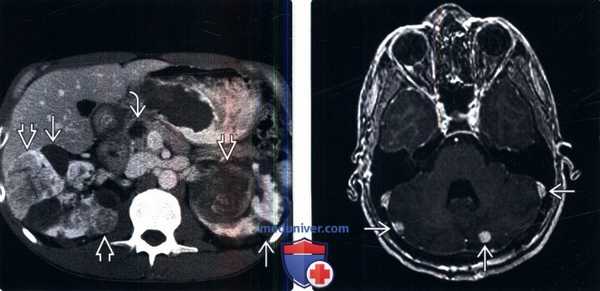

(Слева) КТ с контрастированием, аксиальная проекция: у пациента с болезнью Гиппеля-Линдау выявлены множественные двусторонние кисты почки и ПКР. Выявлено кистозное новообразование в головке поджелудочной железы. Поджелудочные проявления болезни Гиппеля-Линдау включают кисты, кистозные новообразования (микрокистозная аденома) и нейроэндокринные опухоли.

(Справа) МРТ, постконтрастное Т1-ВИ, аксиальная проекция: выявлены множественные контрастируемые патологические изменения мозжечка, что позволяет предположить гемангиобластомы.е) Клинические особенности: